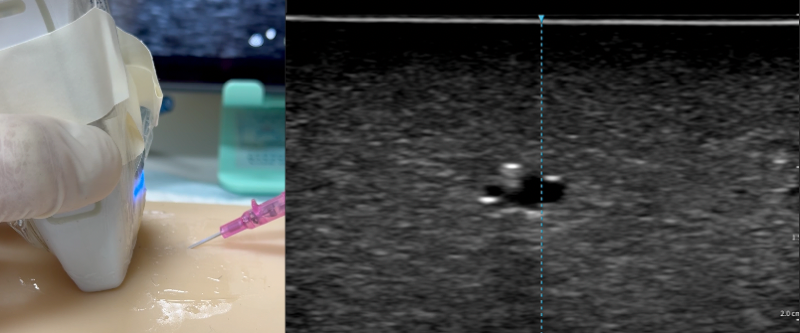

- Stop the needle and slide the probe away

- Slide the probe: Slide the probe distally until the dot disappears. Do not tilt the probe.

- The needle tip within vessel showing as the “bull’s eye”